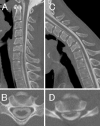

We herein describe a 37-year-old man who developed cervical flexion myelopathy 11 years after suffering a cervical spinal cord injury. Cervical magnetic resonance imaging 11 years after the accident demonstrated atrophy and hyperintense lesions at the C6 and C7 levels in the cervical cord with an abnormal alignment of the vertebrae. In the neck flexion position, an anterior shift of the cervical cord was evident. Our patient's condition suggests that an abnormal alignment of the cervical spine and spinal cord injury due to a traumatic accident could be risk factors in the subsequent development of cervical flexion myelopathy.